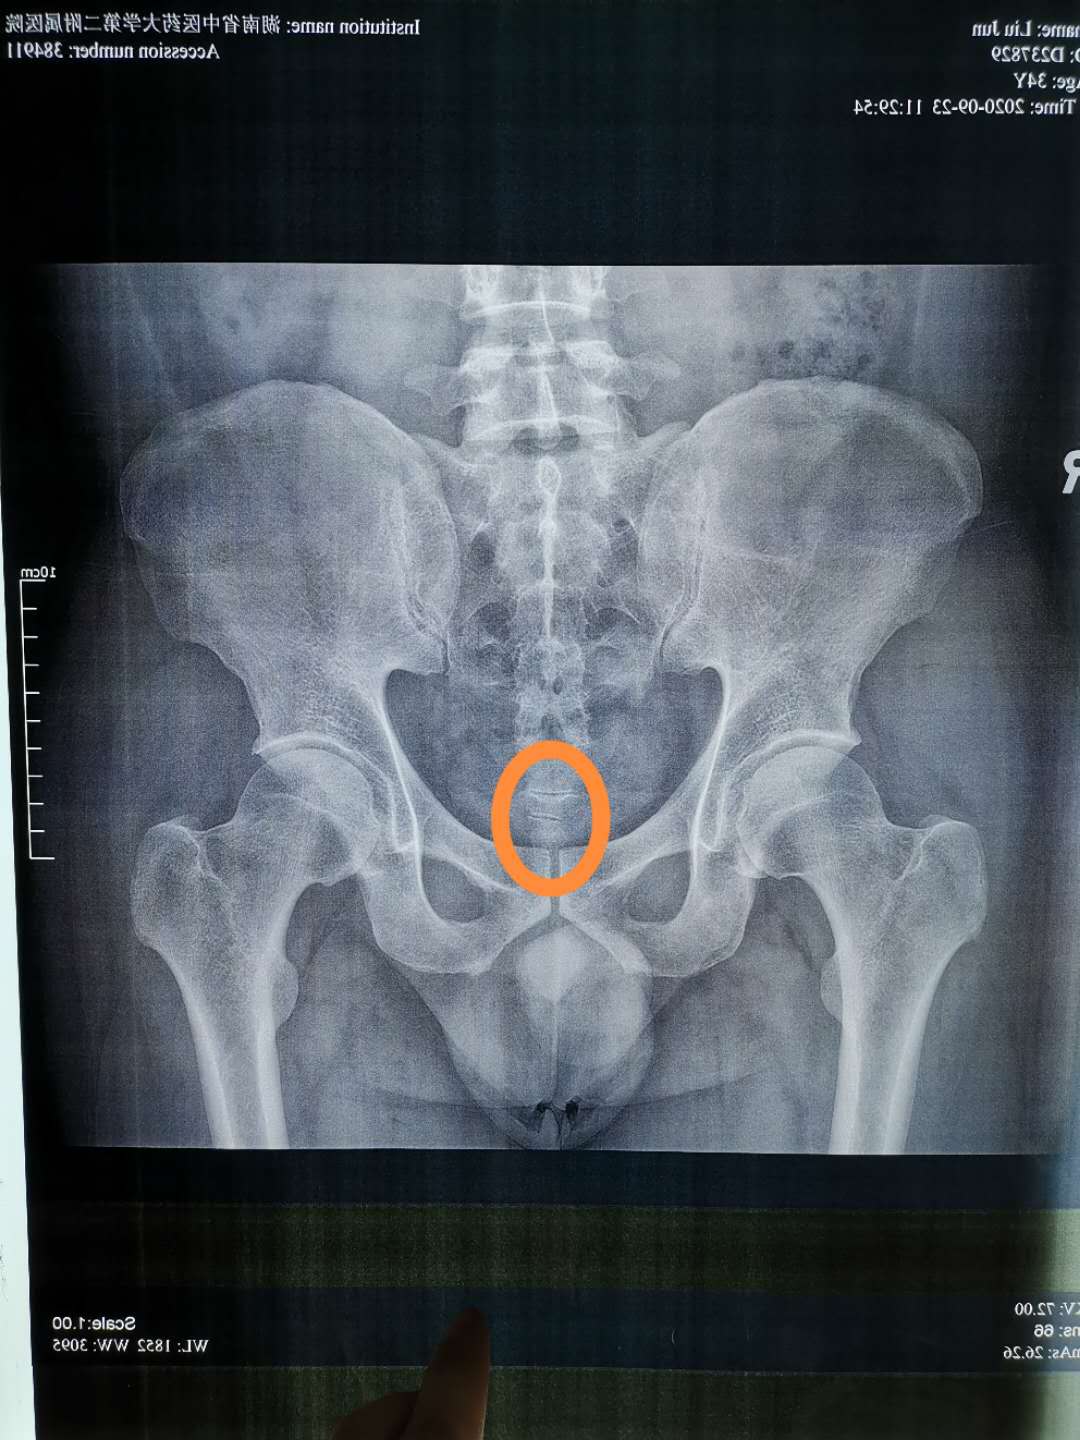

患者俯卧于床,我从在骶尾骨触诊,发现尾骨不在臀裂正中线上,偏于左侧,尾骨尖右侧有明显压痛点,嘱其查骨盆正位片,可以看到影像学确实如此。

那么患者尾骨部两侧的肌肉肯定时不平衡的,尾骨在*力暴**作用下偏于左侧,那么右侧连接于尾骨的肌肉就会被动拉伸紧张,就会形成筋结点,我在筋结点处下针解结。